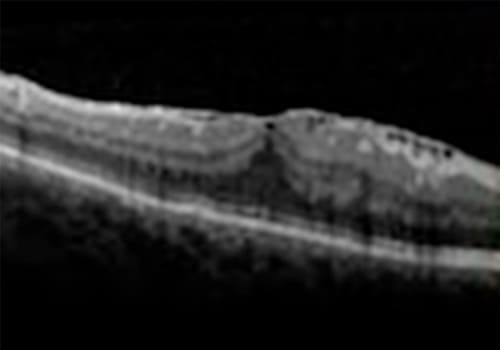

•Tomografia de coerência óptica (OCT)